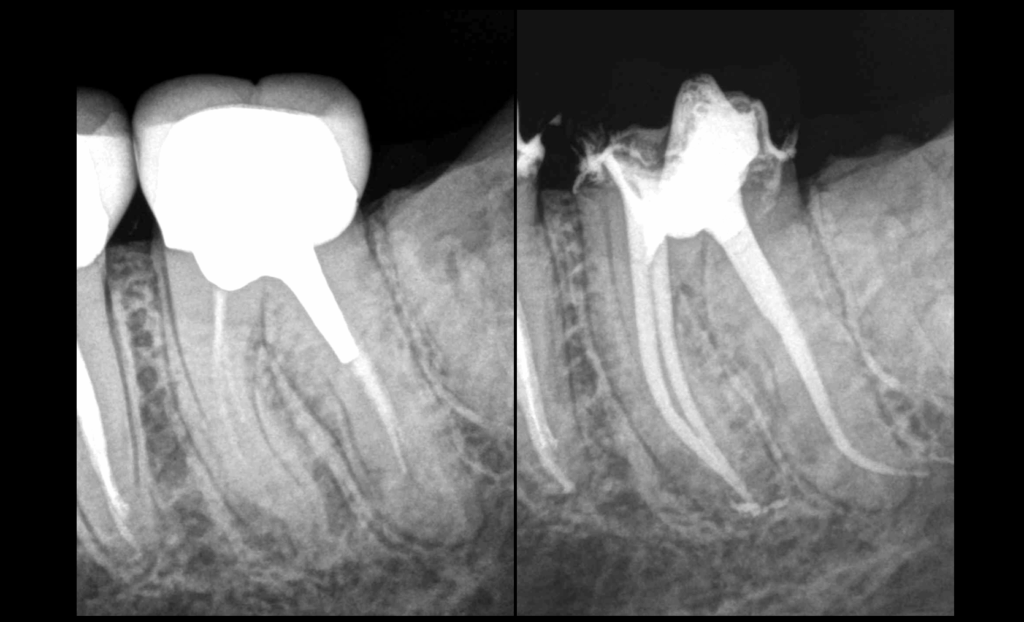

✅ Notre correspondant a déposé la couronne et validé le fait qu’une nouvelle prothèse était bien réalisable.

⚠️ Dans le cas contraire, l’avulsion aurait été indiquée.